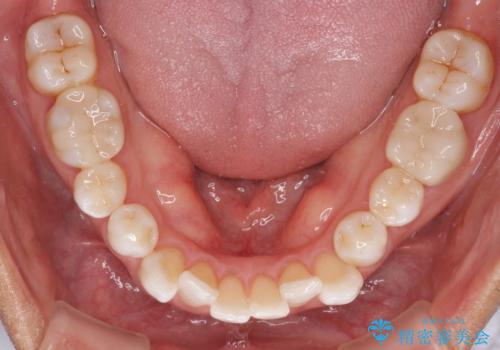

- 治療途中の前歯と上下前歯のデコボコ気にして来院された患者様です。

前歯のデコボコはインビザラインにより歯列を整え、その後に、前歯などをオーダーメイドタイプのオールセラミッククラウンにて補綴治療することとしました。

長時間のマウスピース装着に協力いただき、短期間で歯列をしっかりと改善することができました。

ホームホワイトニングを併用していただいたので、とても明るい口元に仕上がり、患者様には大変満足していただきました。